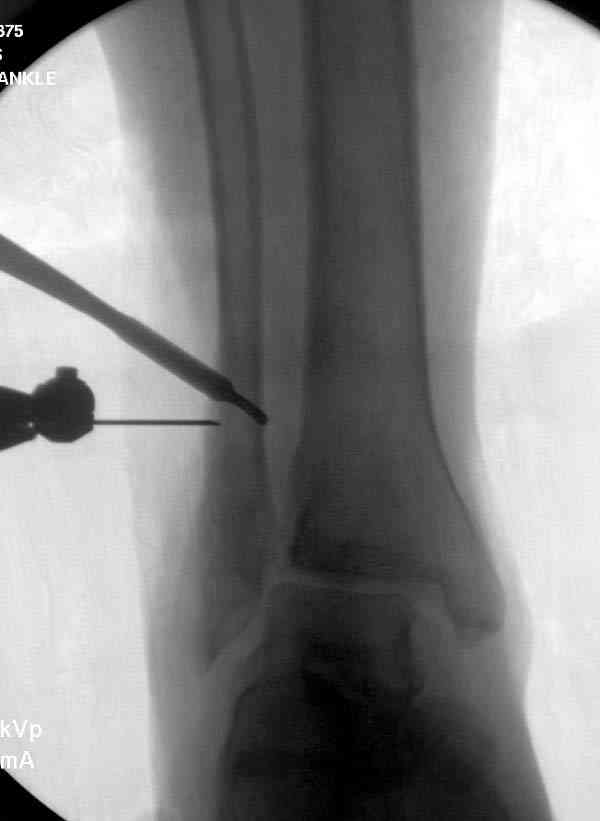

Проведена обычная стандартная процедура по исправлению неудовлетворительного состояния голеностопного сустава, где кроме удлинения малоберцовой с применением compression tension device за проксимальный конец пластины, проведено замещение трикортикальным графтом из крыла, освобождение синдесмоза и медиальной щели от

фибротических масс с фиксацией.